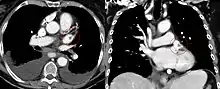

The left atrial appendage can be seen on a standard posteroanterior X-ray, where the lower level of the left hilum becomes concave.[11] It can also be seen clearly using transesophageal echocardiography.[12] The left atrial appendage can serve as an approach for mitral valve surgery.[13] The body of the left atrial appendage is anterior to the left atrium and parallel to the left pulmonary veins. The left pulmonary artery passes posterosuperiorly and is separated from the atrial appendage by the transverse sinus.[14] With certain conditions such as atrial fibrillation,[10] the left atrial appendage may be associated with risks of stroke from blood clot formation, because of which surgeons may choose to close it during open-heart surgery, using a left atrial appendage occlusion procedure.[15]